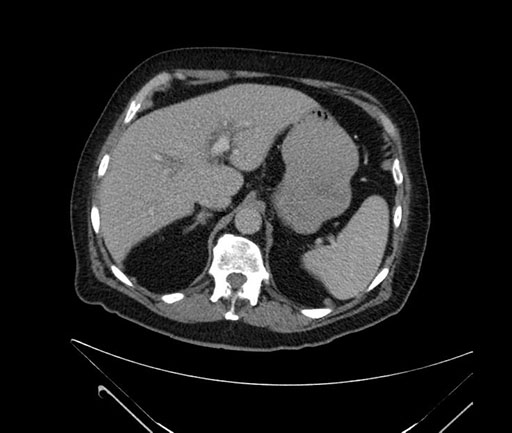

Imaging Analysis

Look through the patient's CT scan to identify any areas of concern for the necessary procedure.

Based on your CT findings, which issue(s) would give reason for "planned slowing down moment(s)" in this case?

Considering a standard Whipple procedure, what step(s) of the operation would you do differently in this case?